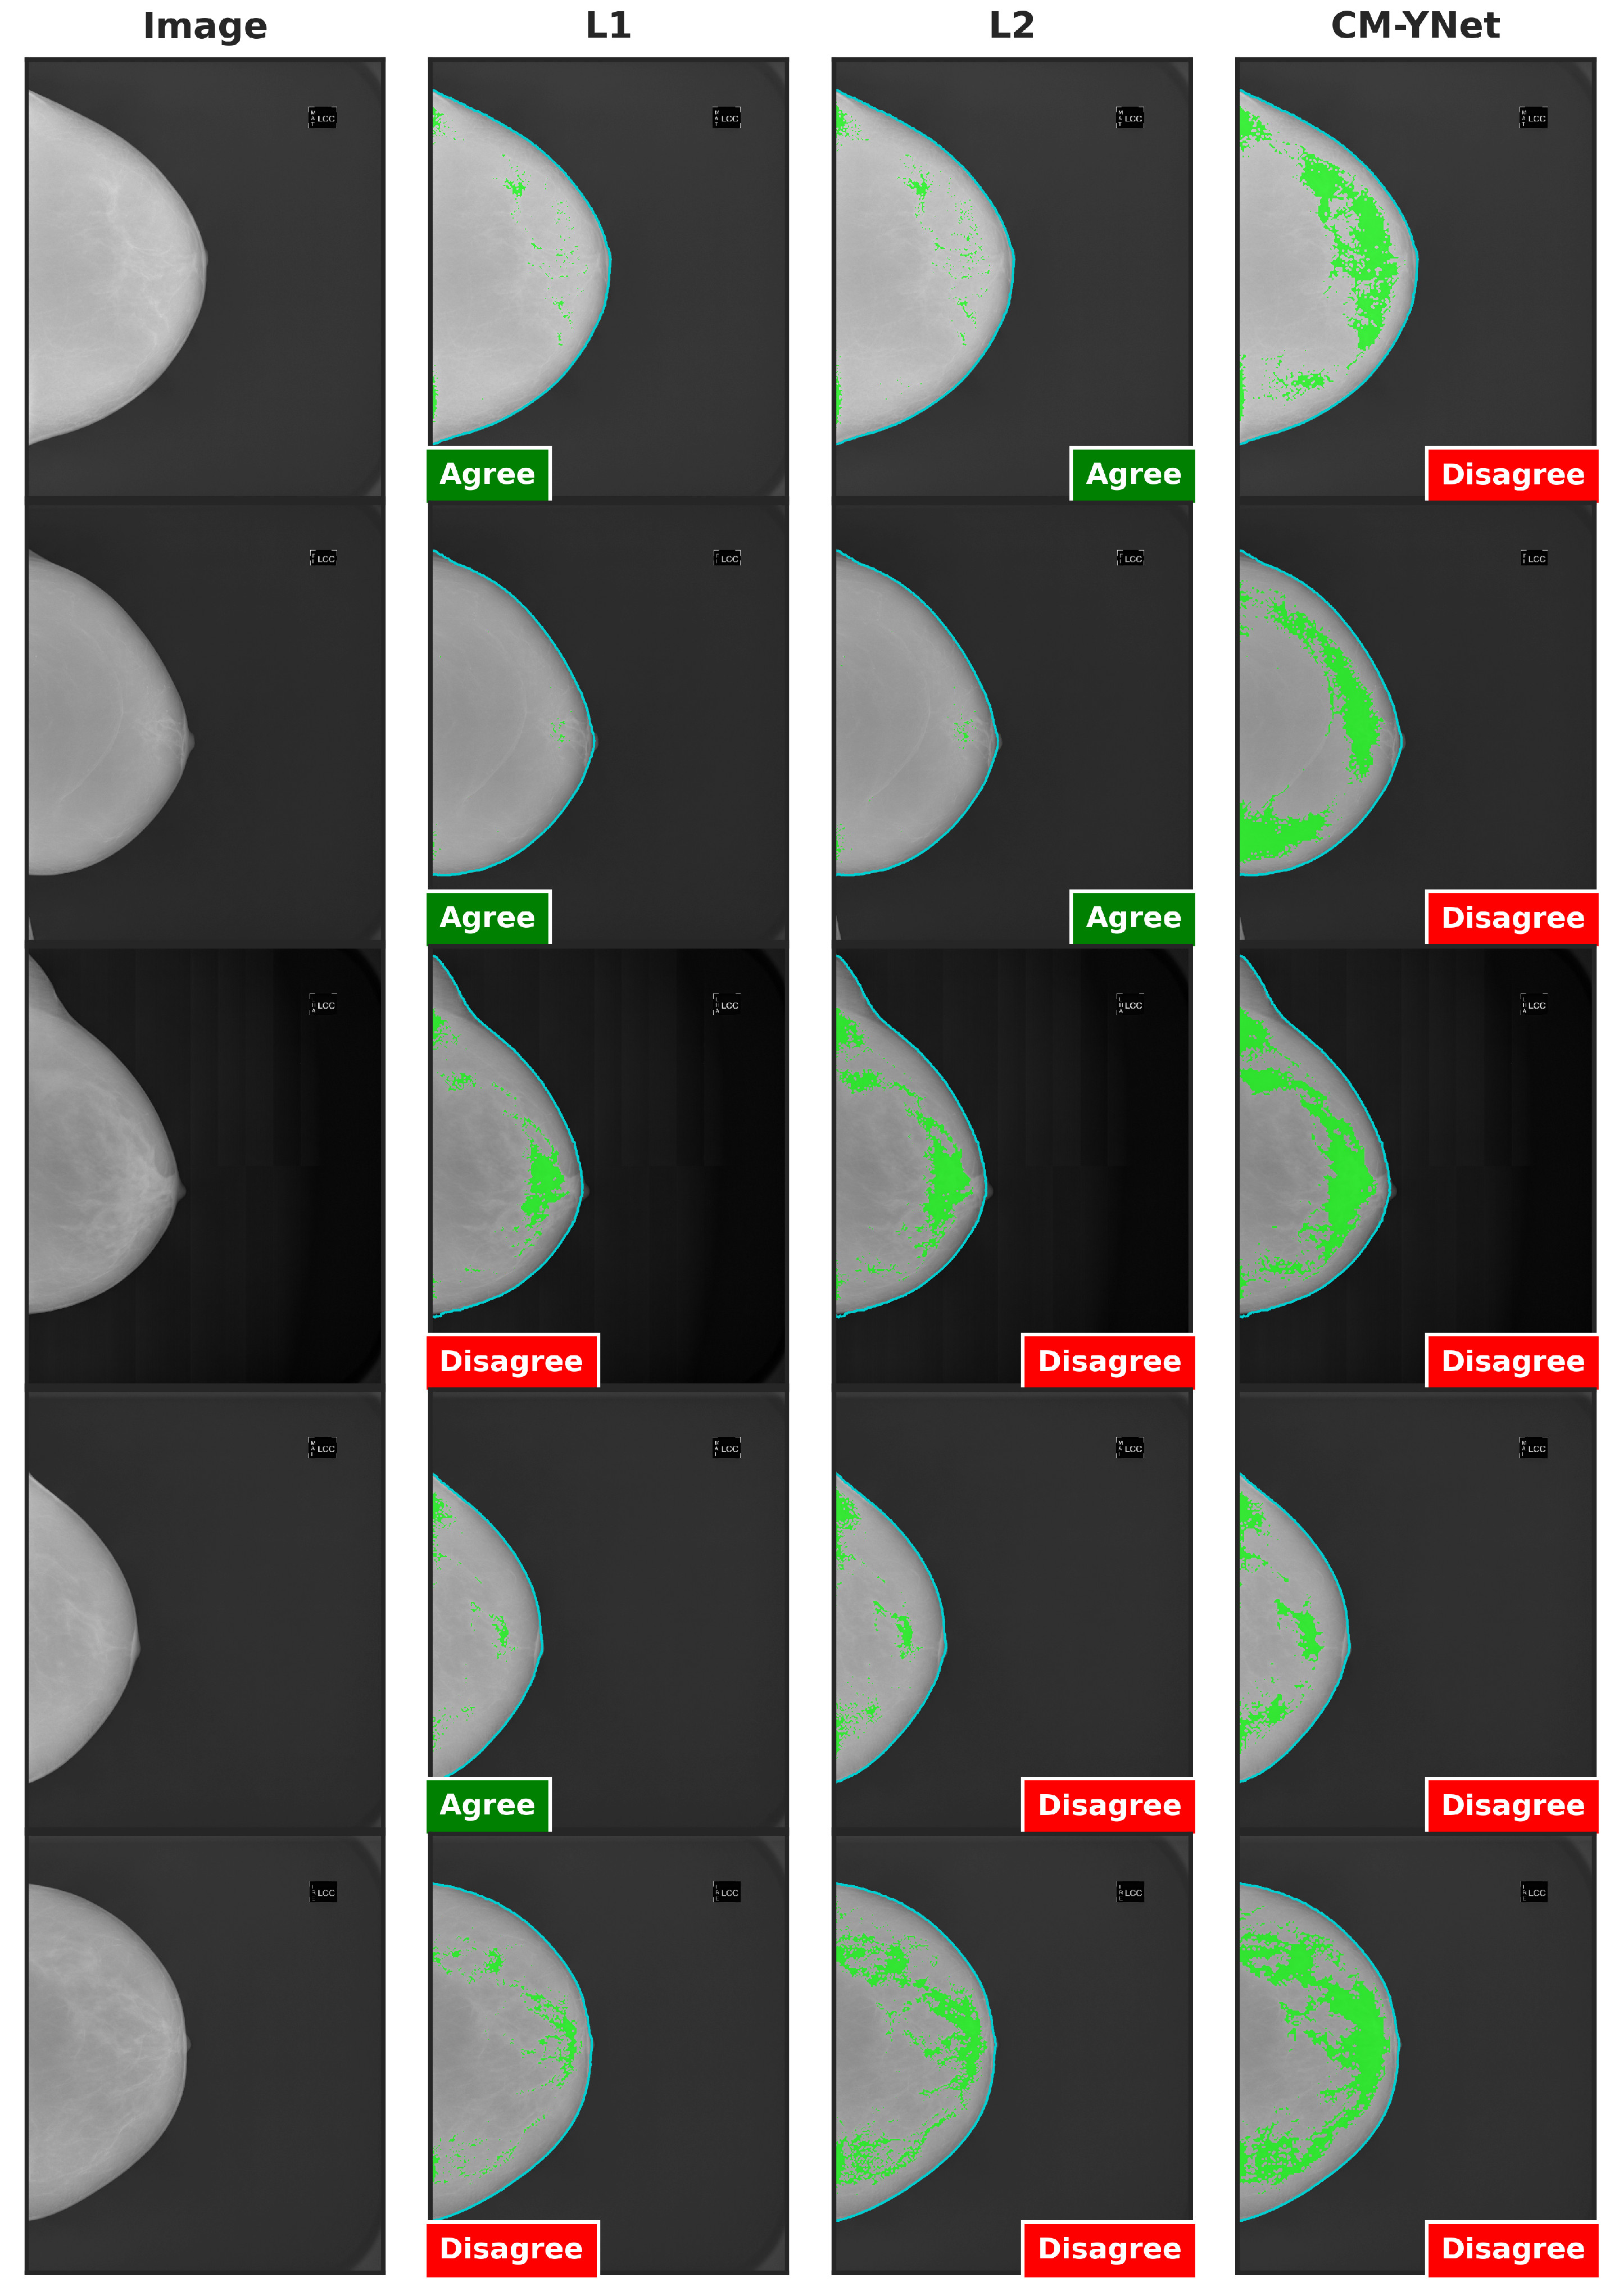

Figure 9 presents examples of images segmented by CM-YNet where V1 disagreed with the automatic segmentation in both evaluations of the same segmentation. This disagreement was observed in 16 out of 300 images, as depicted in Figure 8. Notably, these images were acquired using older devices (HOLOGIC and LORAD in Figure 3), which could explain the increased difficulty in accurately segmenting these lower-quality images, even for expert annotators.

Figure 9.

Examples of segmentations that were shown twice to V1 to analyze the intra-observer variability. In these examples, V1 indicated disagreement with CM-YNet on both occasions.

Further analysis of the intra-observer confusion matrices (Figure 5), which reflect the consistency of each validator’s repeated assessments using binary labels (Agree vs. Disagree), reveals that the segmentations originally labeled by L1 exhibit the lowest intra-observer agreement. This indicates that the validator (V1) was less consistent when evaluating L1’s segmentations, potentially due to greater variability or ambiguity in those masks. In contrast, CM-YNet’s segmentations, although not always labeled as correct, were assessed more consistently by V1 across repeated validations. These results suggest that consistency in evaluation may not always align with accuracy and that model-generated masks can elicit more reproducible judgments even if they are more frequently judged as incorrect.

Figure 10 shows two examples where V1’s decisions changed depending on the order in which the segmentations were presented to them during the validation process, even though the segmentations from the three labelers were visually similar. Importantly, the order discussed here refers to the sequence in which the segmentations appeared to V1, not the fixed column order used in the figure layout. In the first-row example, the segmentation by L1 was shown first to V1, who marked it as agreement; however, V1 later marked disagreement for the same image when it reappeared with segmentations by L2 and CM-YNet. In the second-row example, V1 initially marked disagreement for the first two segmentations they saw (L1 and CM-YNet) but later marked agreement for the third (L2).

Figure 10.

Examples of segmentations where V1 changed his opinion over time: from agree to disagree (first row), and from disagree to agree (second row). Although the visual layout follows a fixed column order (original image, L1, L2, and CM-YNet), the validator viewed the segmentations in a different sequence. For the first-row example, the presentation order was L1, L2, CM-YNet; for the second-row example, it was L1, CM-YNet, L2.

These observations were corroborated by V1, who was consulted about these specific examples without indicating him the order of appearance:

- Example 1: “In the inner quadrants of the three images something that is not dense tissue is segmented, so they would be oversegmented, but they also do not include all the glandular tissue of the breast, so they would also be undersegmented. We could consider them incorrect. At some point, I probably concluded that the machine or the labelers could not avoid including something from the inner quadrants without sacrificing the fibroglandular tissue, and that is why I marked the first one as correct It would be good to know in what order I read them”.

- Example 2: “The three images seem to be oversegmented. It may be that I marked L2 as correct because I evaluated it last and understood that it was difficult not to include the pectoralis major since the dense tissue was so well delineated in the segmentation. In this case, it would be good to know in what order I read the three images”.